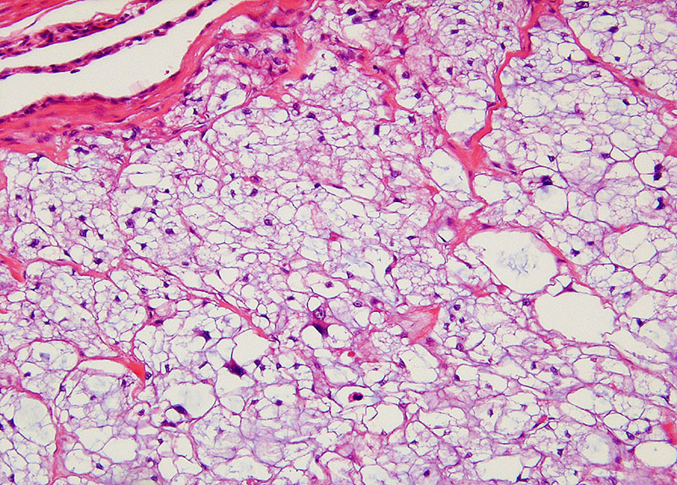

脊索腫の確定診断は、生検組織の病理組織学的検査と、免疫組織化学(IHC)染色によって行われます。組織病理学的に、脊索腫は被膜を持たず、結節状で、真皮内に緩やかに配置された新生物として観察されます 。腫瘍細胞の小葉構造が線維性組織と混在し、線維性組織内にはムチンと一致する豊富な細胞外好塩基性物質が存在します 。腫瘍細胞はしばしば脂肪細胞に似た空胞を持つ泡状細胞で構成され、周囲の皮下組織や骨髄腔に浸潤し、骨組織の著しい破壊と置換を引き起こします 。 脊索腫は、その起源から上皮系と間葉系タンパク質の二重発現という特徴を持ちます。

IHC検査は、この特徴を利用して、脊索腫と軟骨肉腫を明確に鑑別するために実施されます。 鑑別に決定的なマーカーはサイトケラチンで、 脊索腫はサイトケラチン陽性で、一方、軟骨肉腫はサイトケラチンが陰性となります〔Dunn et al.1991,Herron et al.1990〕 。